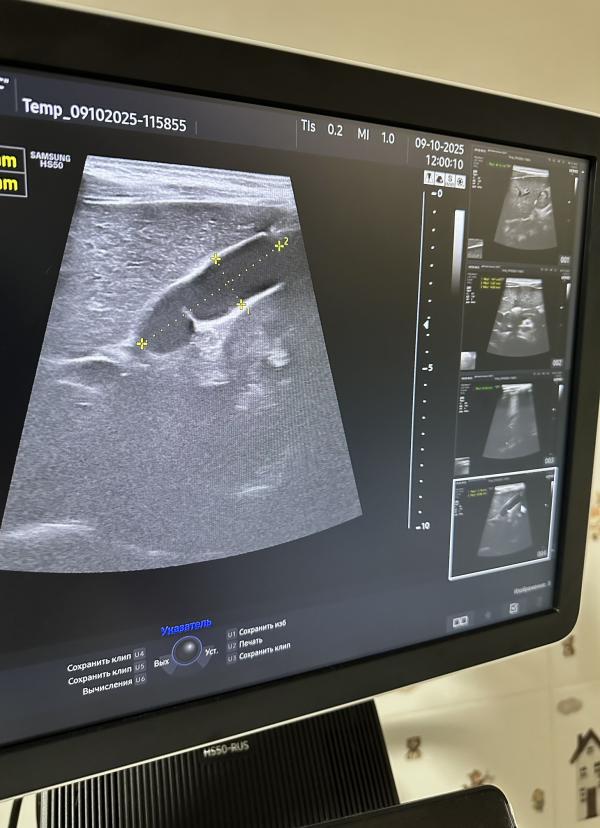

Желчный пузырь — небольшой мешочек, расположенный под печенью, предназначенный для хранения жёлчи, вырабатываемой печенью. Форма желчного пузыря обычно грушевидная, овальная или округлая. Иногда форма может меняться, приобретая перегибы, перетяжки или дополнительные складки. Такое явление называют деформацией желчного пузыря.

- Перегиб шейки желчного пузыря;

- Изгиб дна или тела пузыря;

- Формирование перегородок внутри органа.

*на сканах представлены разные желчные пузыри

Пока в просвете желчного пузыря отсутствуют признаки патологических изменений, таких как наличие желчи, конкрементов (камней) или новообразований, поводов для беспокойства нет